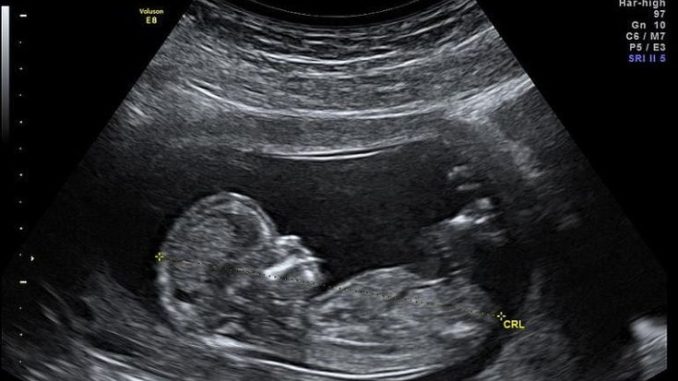

- Ultrasonografi (USG) USG adalah metode umum yang sering dilakukan selama kehamilan untuk memeriksa kondisi janin. USG dapat membantu mendeteksi kelainan fisik atau perkembangan yang tidak normal.

- Biaya USG: Kisaran biaya USG di klinik dan rumah sakit bervariasi antara Rp200.000 hingga Rp1.000.000, tergantung pada fasilitas dan apakah dilakukan USG 2D, 3D, atau 4D.